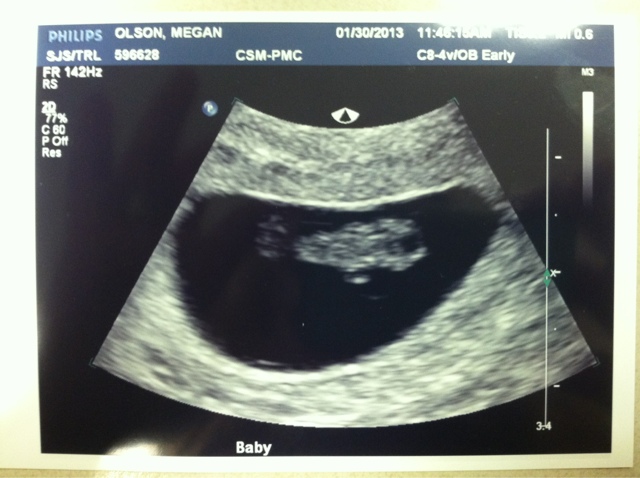

We had our first ultrasound today! Oh man was it exciting. We saw your heart beat, which is such an amazing thing. It's so great to know that everything is looking good so far. Your little heart was beating between 149 and 154 bpm. (It's supposed to be between 140 and 180. So perfect.) They moved up the due date a few days to September 15. So, I was actually at 7 weeks few days ago.

The technician called you a little gummi bear (love) and said you're about 1.1 centimeters large. They tell you to drink 32 ounces of water an hour before your appointment. I guess a full bladder really helps them see everything. The technician kept commenting on how full my bladder was. "Oh wow, that's a full bladder," he kept saying. It was really funny, but pretty unbearable at the same time. I constantly have to pee nowadays and a really full bladder is no fun. After we left, Matt said we should've asked him if that was the fullest bladder he'd ever seen. :)

To get better pictures, they also stuck a little camera through the birth canal. Obviously it was super uncomfortable, but no different than a PAP. Matt kept asking if it was weird or if I felt weird with the two technicians being the room. And I told him honestly that the annual gyno appointment is way worse.

It was honestly so great to see your little heart beat. It is so reassuring. I guess the chance of miscarriage goes down even more now that they were able to see that.